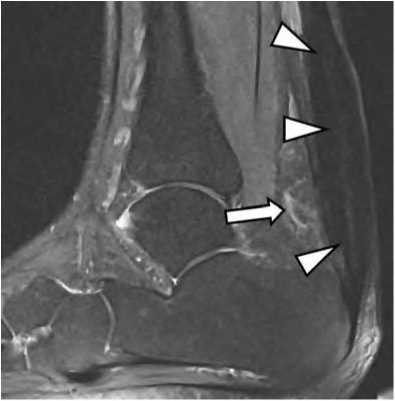

Рис. 2. Хронический тендиноз и перитендиноз ахиллова сухожилия.

На FS PD FSE томограмме в сагиттальной проекции определяется неравномерное утолщение сухожилия (треугольные стрелки), отек окружающей жировой ткани (обычная стрелка).

На МРТ обычно визуализируются жидкостной компонент и синовиальные разрастания в проекции дистальной части межберцового синдесмоза, внутри канала латеральной лодыжки, по передней и задней поверхностям голеностопного сустава, по ходу таранного синуса, которые имеют среднюю и высокую интенсивность сигнала в PD FSE импульсных последовательностях и отчетливо выявляются на томограммах с подавлением сигнала от жира (рис. 5).

Чувствительность МРТ в первичной диагностике импинджмент-синдрома при наличии выраженной клинической картины и в острый период воспаления составляет 92-94%, снижаясь до 56-60% при стихании симптомов [4]. С учетом этого, исследование целесообразно назначать в острый период заболевания, а также для контроля регрессии изменений на фоне лечения.